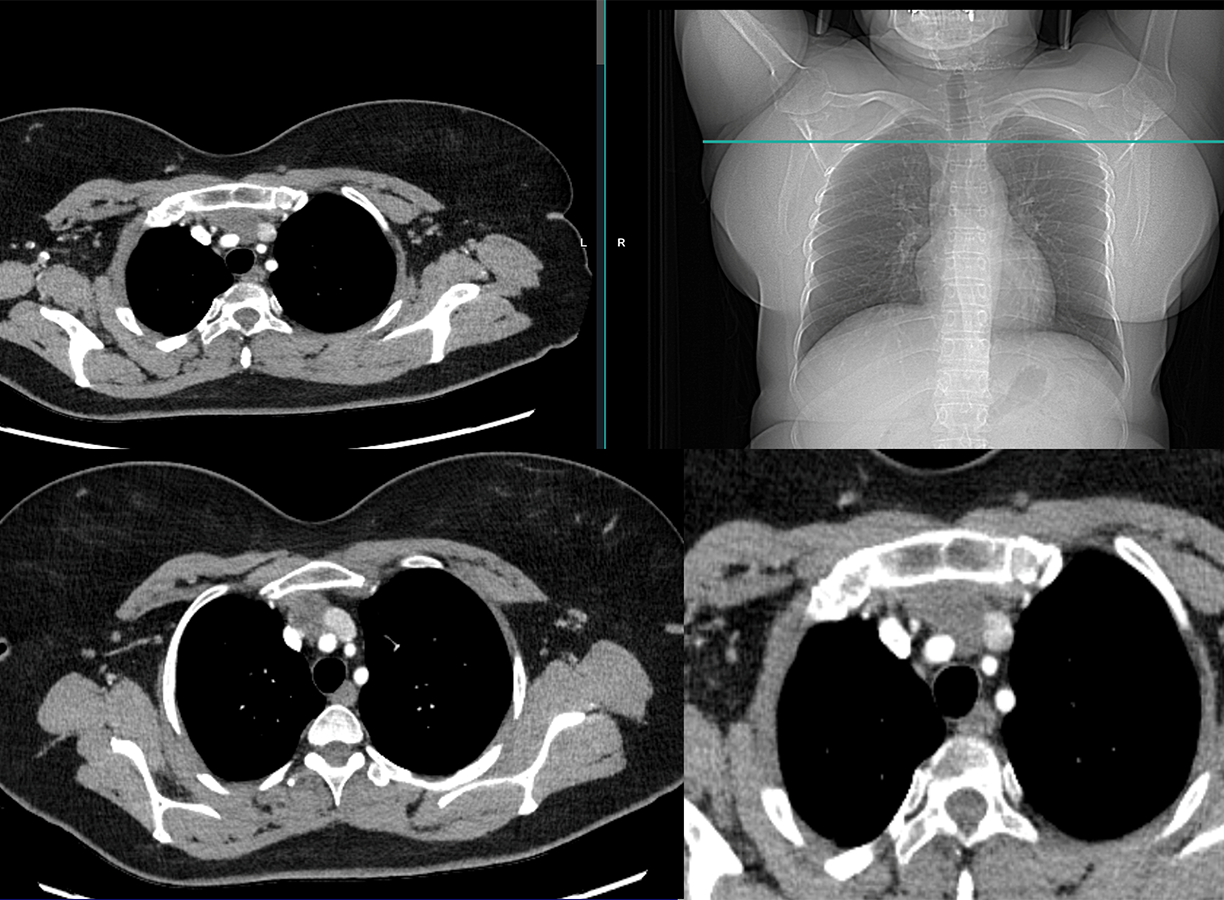

Masse 38 x 21 x 24mm

Parenchyme pulmonaire - pas de nodule - Pas d'épanchement des séreuses - Hépatomégalie homogène